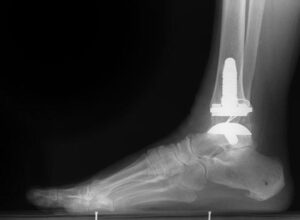

Total ankle replacement, or arthroplasty, is a surgical procedure where the damaged cartilage and bone in the ankle joint are removed and replaced with metal or plastic components. These artificial joint surfaces are designed to restore movement and improve overall joint function. While total ankle replacement is less common than similar procedures for the hip or knee, advancements in implant technology have significantly improved outcomes. Modern designs make this option increasingly viable for individuals seeking to alleviate pain and regain mobility in the ankle joint.

An X-ray of a total ankle replacement (arthroplasty).